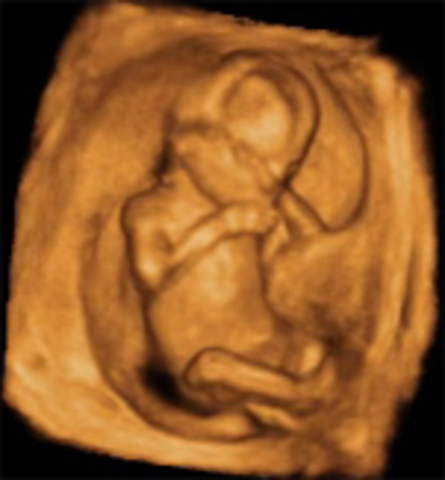

El feto a estas semanas empieza a ubicarse en la posición definitiva que tendrá al nacer, que en la mayoría de los casos es con la cabeza hacia abajo a pesar de que puede cambiarla hasta el momento del parto. En algunos caso los fetos se posicionan de nalgas o situación transversa debido a una falta de movilidad por un cordón umbilical corto o enredado en el feto, por la forma del útero materno o simplemente porque se siento mucho mejor en esa posición.